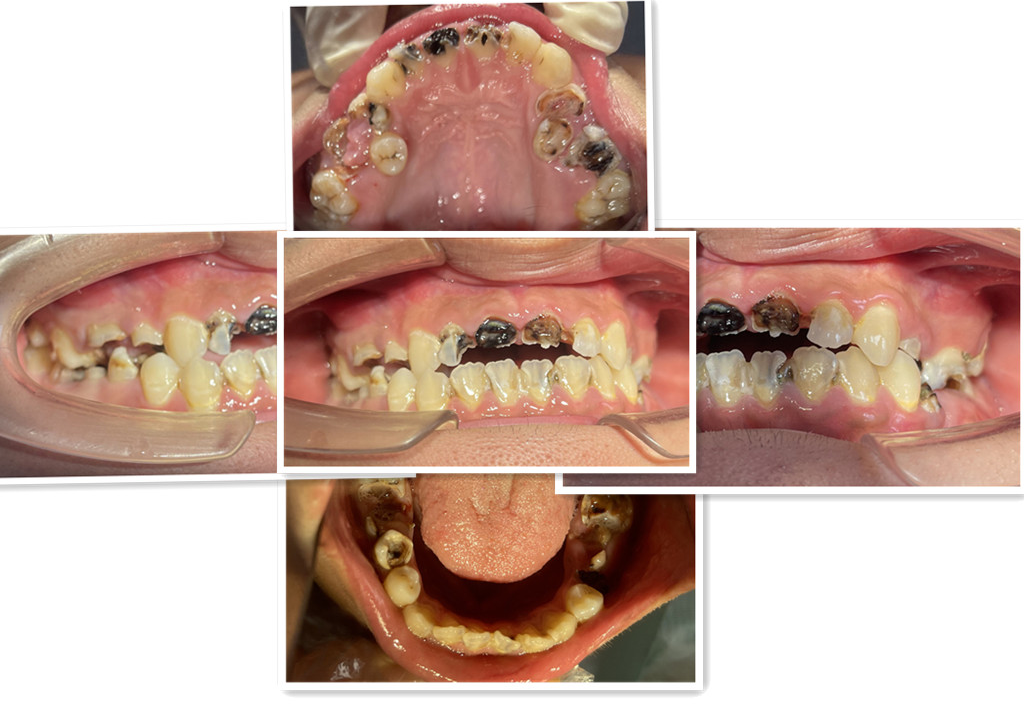

近日,广州市花都区人民医院口腔科通过规范的诊疗流程,为一名18岁男孩完成牙齿“蜕变”,让其重拾自信笑容。

这名男孩就诊时满口黑牙,颜值大打折扣。广州市花都区人民医院口腔科结合放射检查、内科治疗、外科干预及修复重建等诊疗环节,制定了“拍片检查—牙周治疗—拔牙—根管治疗—桩冠修复”的系统性方案,后续还将为其缺失牙进行种植修复。